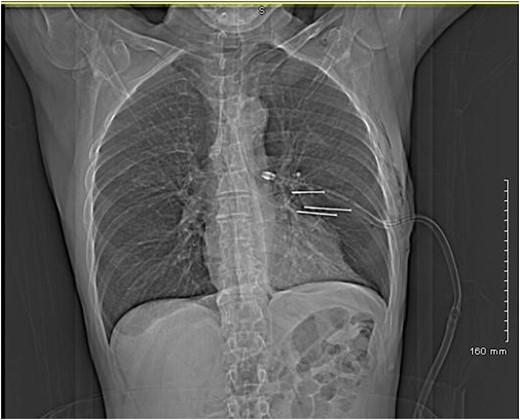

A 64-year-old man referred to our institution with self-inflicted penetrating chest injuries with an electric nail gun. This was in response to express his frustration towards an expensive non-functioning product purchase. Patient used an electric driller to fire in three nails on the chest between left anterior axillary line and left lateral sternal border. Upon arrival to emergency department, on initial assessment according to ATLS protocol, his Glasgow coma score (GCS) was 15, hemodynamically stable with three puncture wounds in his chest medial to his left nipple. He also sustained full thickness electrical burns on the left middle and index fingers and fractured right middle, ring and little fingers. Chest radiograph showed three nails of close proximity to the heart, and a left sided pneumohaemothorax. A chest drain was inserted and a CT thorax was performed (Figs 1 and 2).

The patient underwent a sternotomy for removal of the three nails. Two nails were easily visible and removed. They caused pericardial perforation and myocardial injury. The third nail was difficult to locate. Myocardial injury showed a trajectory near the junction of the left anterior descending artery and the diagonal artery with no bleeding appreciated. A magnet was then used to locate the third nail which was found to be deep in the hilum of the lung. The magnet was then used to gently ‘milk’ the nail into a more superficial position. Once the nail was more easily accessible, it was removed.